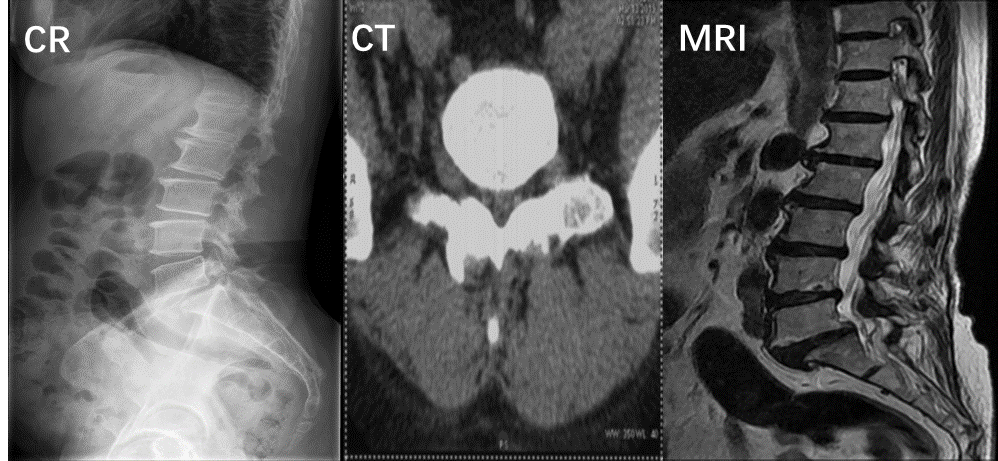

去了医院之后,医生往往建议大家先拍片子,一些朋友非常排斥拍片子,指责医生不拍片子就不会看病了,拒绝拍片。但腰椎的影像学检查是非常有必要的,是医生判断病情的依据。一般包括三个内容:X线、CT和MRI。

X线可以提示腰椎的生理曲度、椎间隙宽度以及椎体间的稳定度。

CT图像可较清楚地显示椎板及黄韧带肥厚钙化、小关节增生肥大、椎管及侧隐窝狭窄等情况。

MRI则可直观地显示椎间盘突出的形态及其与硬膜囊、神经根等周围组织的关系。